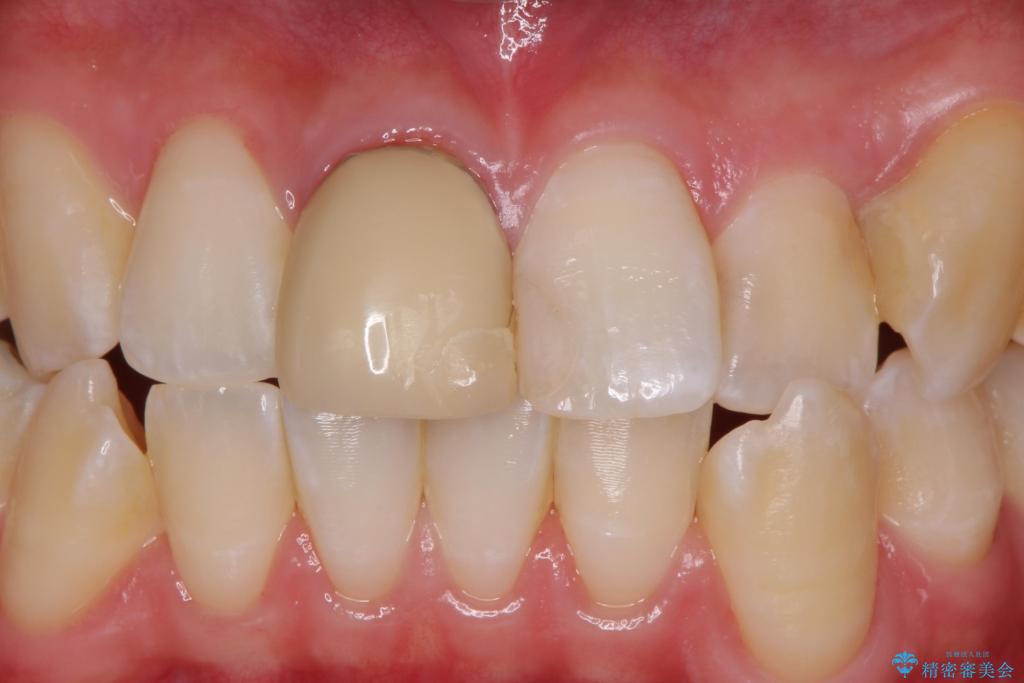

色・形ともに改善され、大変喜んでいただけました。

- 右上1: 仮歯/11,000円、ジルコニアクラウン(スタンダード)/121,000円 合計132,000円(税込)費用は治療当時の料金となります